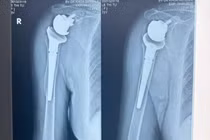

Trong quá trình phẫu thuật, các bác sĩ xác định bệnh nhân bị vỡ lách độ V, tổn thương phức tạp vùng ngực - bụng. Kíp mổ đã: Cắt lách cầm máu; Khâu xử trí vết thương thấu bụng và thấu ngực; đặt dẫn lưu màng phổi hai bên hút liên tục; kiểm soát chảy máu và xử trí toàn diện các tổn thương nguy hiểm.

Trong ổ bụng, kíp mổ đã lấy ra khoảng 2000 ml máu cục và máu loãng, đồng thời truyền 5 đơn vị hồng cầu khối và 05 đơn vị huyết tương tươi đông lạnh để hồi sức cho người bệnh.

Qua kiểm soát sau mổ, các bác sĩ tiếp tục phát hiện bệnh nhân còn có tổn thương vỡ xương bả vai trái và gãy 05 xương sườn bên trái, hiện các tổn thương này đã được theo dõi và kiểm soát chặt chẽ theo phác đồ điều trị chấn thương ngực.